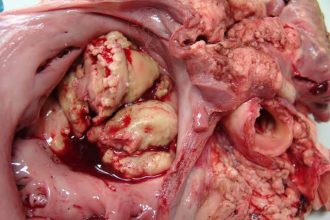

- التهاب الصمامات: يحدث غالبًا بسبب عدوى بكتيرية أو فيروسية، ما يؤدي إلى تلف الصمامات.

التهاب الصمام الثلاثي الشرفات

التهاب الصمام الثلاثي الشرفات هو حالة طبية تؤثر…